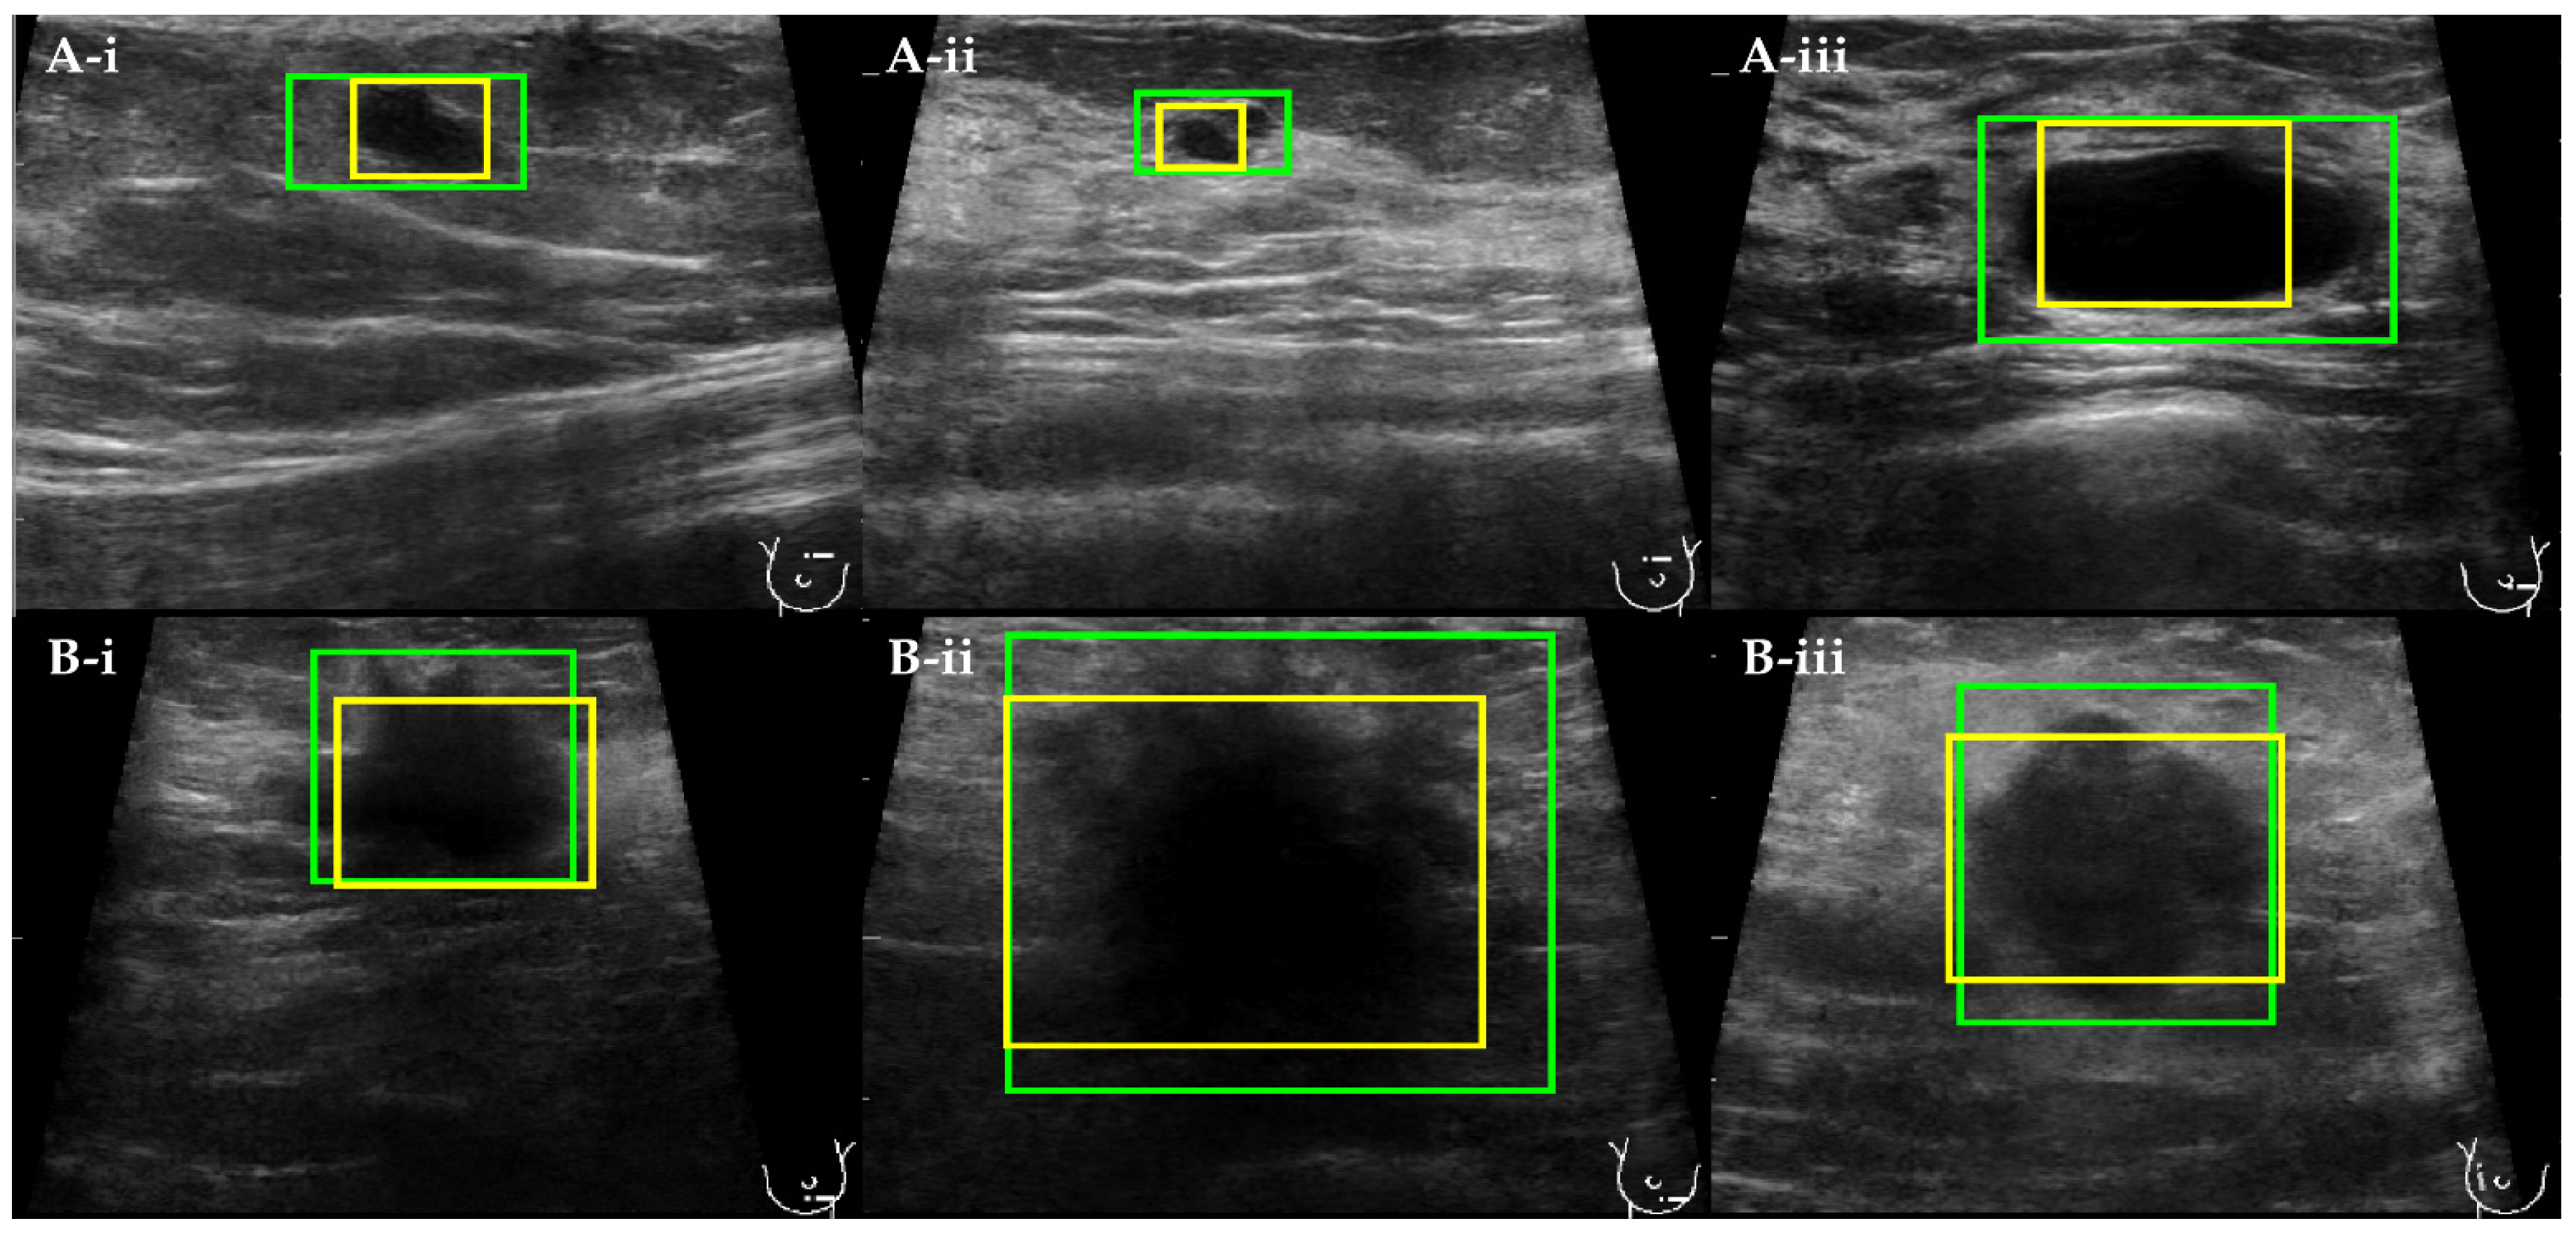

The detection boxes obtained by YOLOv3 are visually bigger than those found by the Viola–Jones algorithm (Figure 4). Furthermore, they comprise not only the breast lesion but also the neighboring tissue. The detection bounding boxes computed by the Viola–Jones algorithm are tighter and, in some cases, bound only part of the breast lesion.

Figure 4. The comparison between automatically computed detections of (A(iiii)) benign and (B(iiii)) malignant breast lesions obtained with YOLOv3 (green) and Viola–Jones (yellow) detection models.

The three RS selected separately for the Manual Segmentation, YOLOv3, and Viola–Jones datasets comprised 33, 51, and 41 descriptive features, respectively (Table 10). The different number of radiomics features selected for each Classification Subset was caused by the following factors: First, all the extracted “segments” have different characteristics. Those outlined by YOLOv3 are bigger and comprise not only the lesion itself, but also the surrounding tissue. By comparison, the segments produced by Viola–Jones are smaller and mainly embed the inner part of the lesion. The segments obtained by the expert radiologist represent the complete shape but miss the tissue adjacent to the tumor. Second, in the feature selection process, different values of the penalty coefficient lambda were found for each of the utilized classification datasets. All of the above resulted in a varying number of features in the obtained RS. Most of the selected features were computed from the derivatives of original US images rather than from the original images themselves (Tables S9–S11).